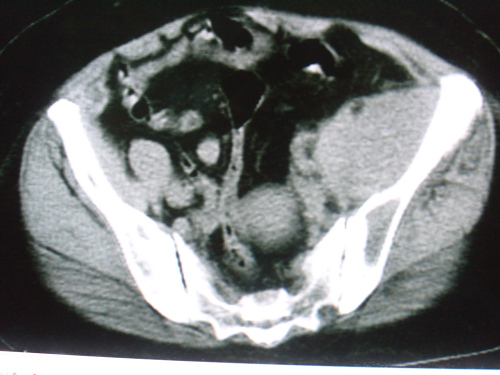

标题: CT18663:女 58岁 左髂区庝痛一年余,加重两月 [打印本页]

标题: CT18663:女 58岁 左髂区庝痛一年余,加重两月

左髂翼内前方软组织样肿块,其密度不均匀,内部呈略低密度的改变,肿块边界清楚,呈宽基底与髂骨“接触”,髂骨骨质破坏。未见明显骨膜反应性增生,及骨旁瘤骨存在。病变不侵犯同侧骶髂关节。

考虑----1 纤维肉瘤-----年龄、表现符合,病变为低度恶性。  或    2  转移瘤-----为髂骨发病率第一病变,需警惕。

左侧髂內肌明显肿大,密度稍不均,可见略低密度的改变,其边界清楚,与髂腰肌间脂肪间隙清晰,与髂骨呈宽基底“接触”,髂骨骨质膨胀性破坏。

考虑左侧髂內肌恶性肿物,建议病检确诊。